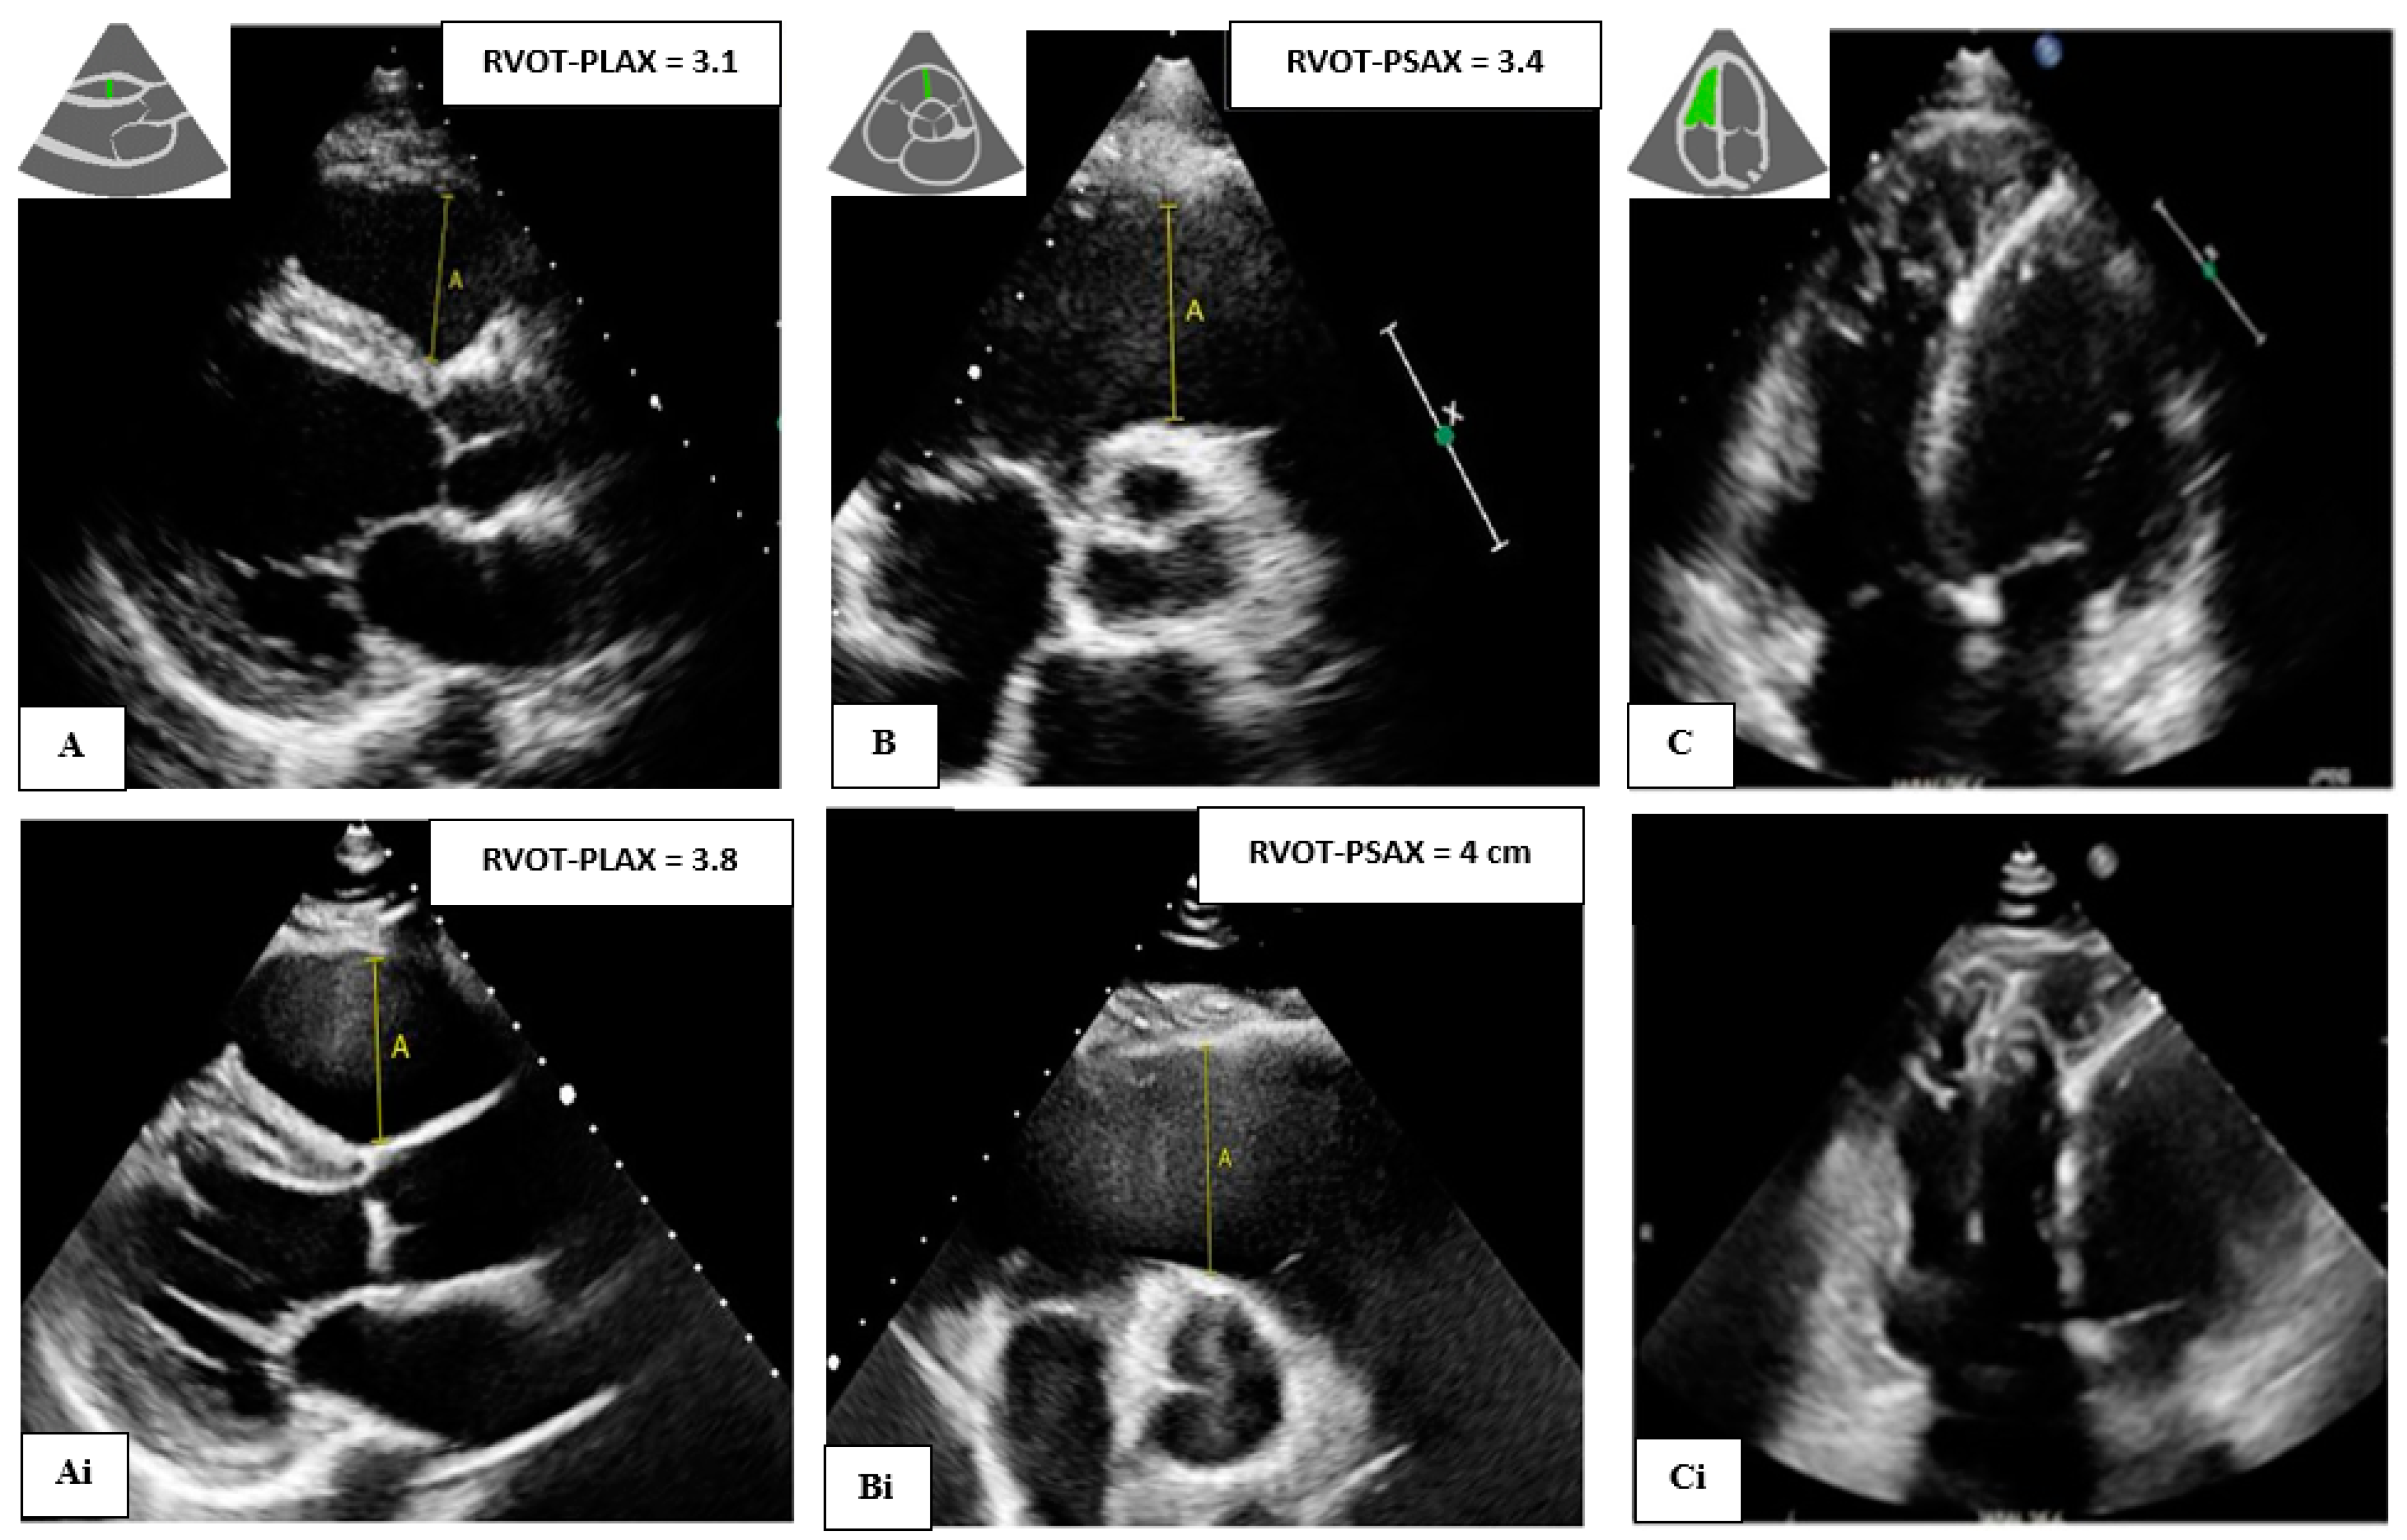

| Echo data | ||||

| RVOT-PLAX (cm) | 3.0 (2.5, 3.5) | 2.7 (2.4, 3.0) | 3.3 (2.7, 4.0) | <0.001 |

| RVOT-PSAX (cm) | 3.2 (2.9, 3.7) | 3.0 (2.7, 3.3) | 3.5 (3.0, 4.0) | <0.001 |